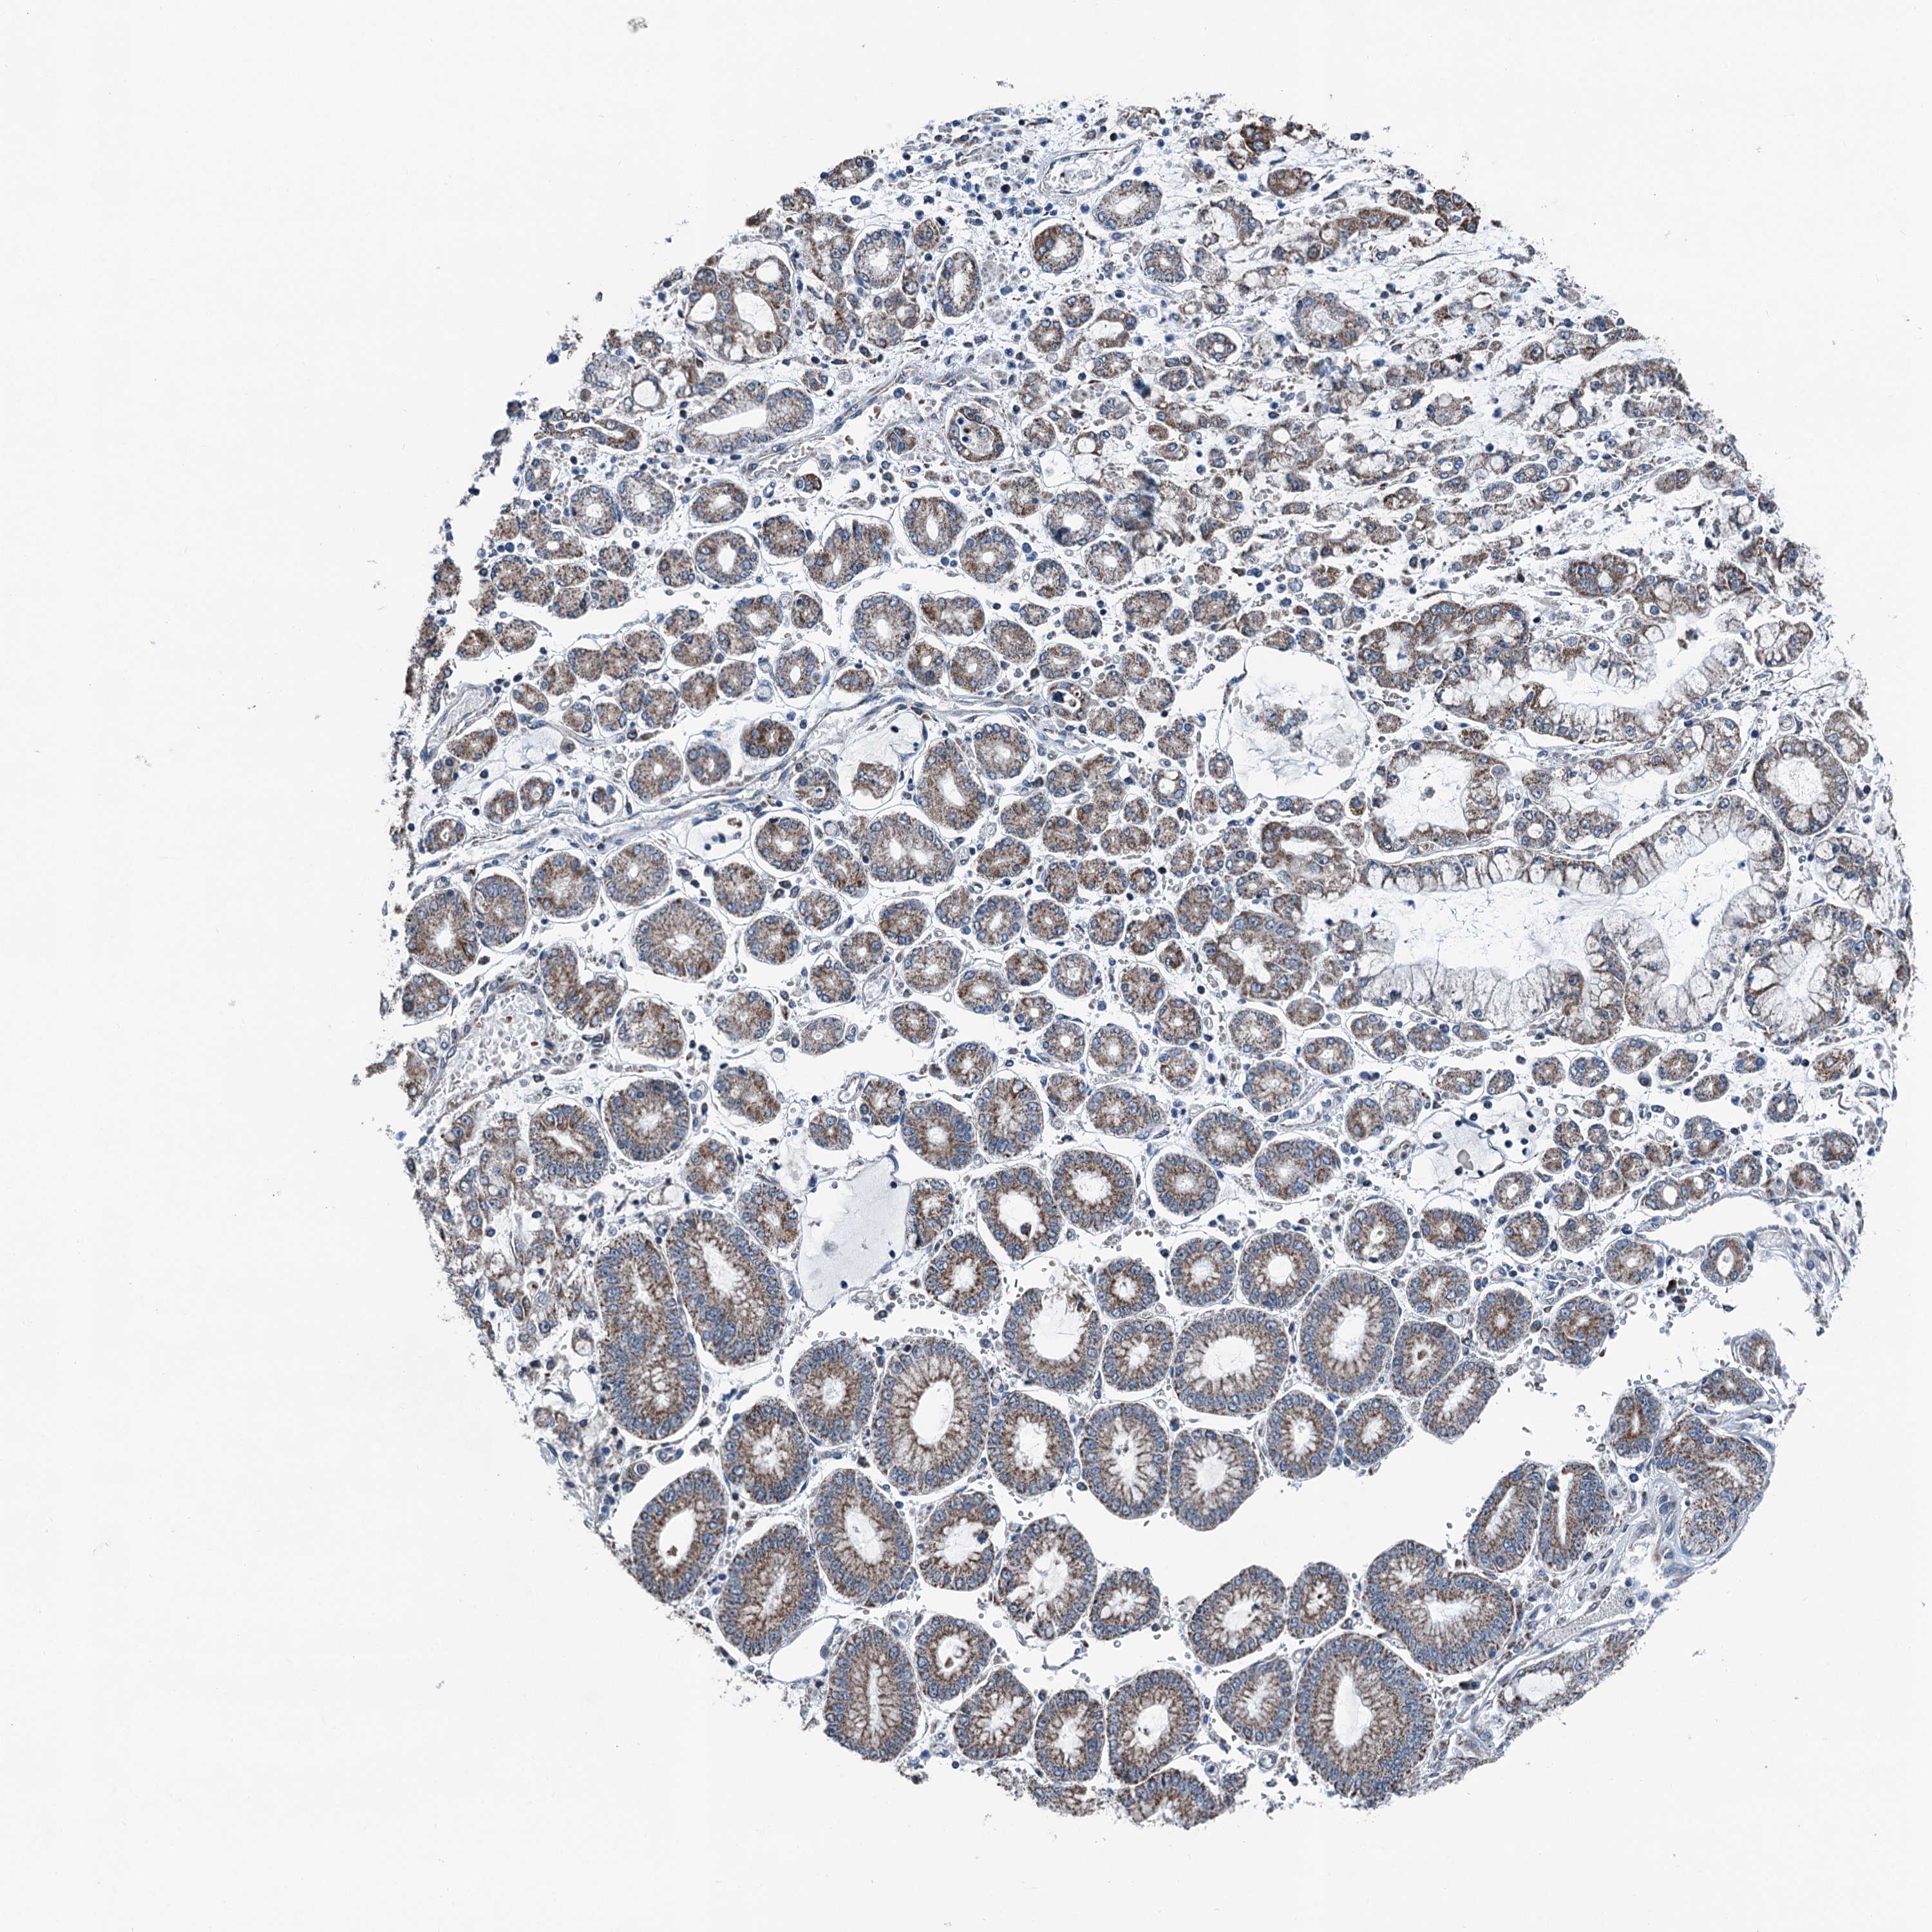

STOMACH CANCER - Protein expressioni

A mouse-over function shows sample information and annotation data. Click on an image to view it in a full screen mode. Samples can be filtered based on level of antibody staining by selecting one or several of the following categories: high, medium, low and not detected. The assay and annotation is described here.

Note that samples used for immunohistochemistry by the Human Protein Atlas do not correspond to samples in the TCGA dataset.

Antibody stainingi

Antibody staining in the annotated cell types in the current human tissue is reported as not detected, low, medium, or high, based on conventional immunohistochemistry profiling in selected tissues. This score is based on the combination of the staining intensity and fraction of stained cells.

Each image is clickable and will lead to virtual microscopy that enables deeper exploration of all samples and also displays staining intensity scores, fraction scores and subcellular localization as well as patient and tissue information for each sample.

Antibody HPA038705

Antibody HPA038706

Staining

High

Medium

Low

Not detected

Intensity

Strong

Moderate

Weak

Negative

Quantity

>75%

75%-25%

<25%

None

Location

Nuclear

Cytoplasmic/membranous

Cytoplasmic/membranous,nuclear

Adenocarcinoma, NOS

Adenocarcinoma, High grade